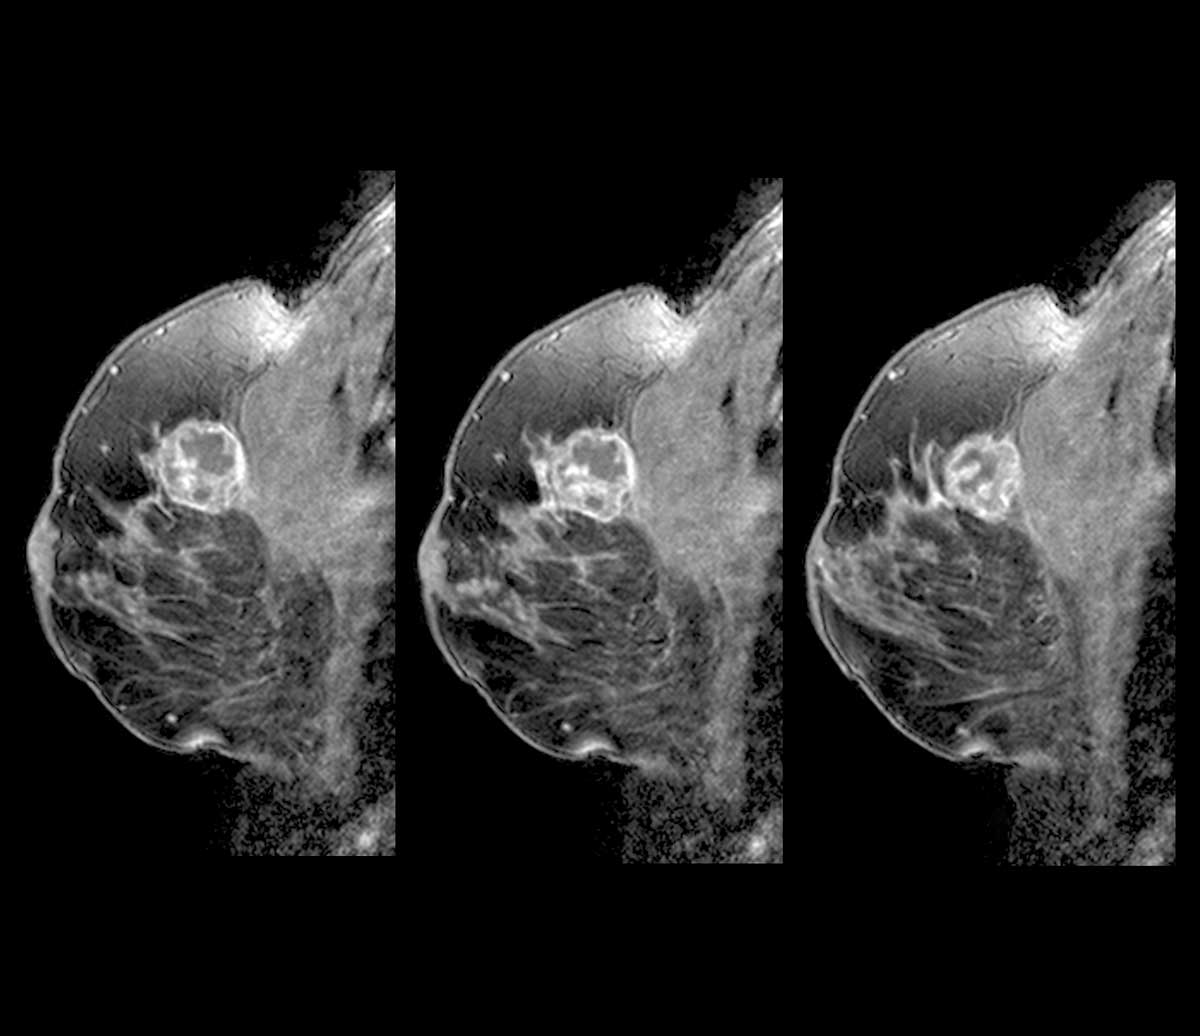

유방 MRI 검사 결과. 기사의 내용과 직접적 연관이 없는 사진./사진=클립아트코리아